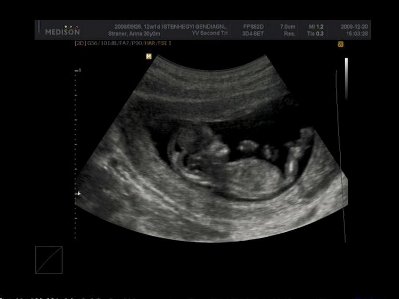

Pann, drukkolok a mai (vagy holnapi?) vizsgálathoz! Így Karácsony előtt csak jó híreket kaphatsz!